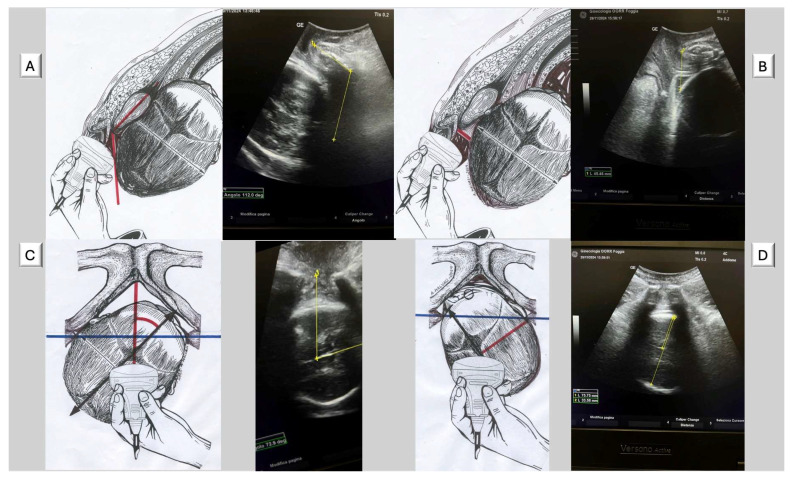

Global cesarean section (CS) rates continue to rise, with the Robson classification widely used for analysis. However, Robson Group 2A patients (nulliparous women with induced labor) show disproportionately high CS rates that cannot be fully explained by demographic factors alone. This study explored how the Artificial Intelligence Dystocia Algorithm (AIDA) could enhance the Robson system by providing detailed information on geometric dystocia, thereby facilitating better understanding of factors contributing to CS and developing more targeted reduction strategies. The authors conducted a comprehensive literature review analyzing both classification systems across multiple databases and developed a theoretical framework for integration. AIDA categorized labor cases into five classes (0-4) by analyzing four key geometric parameters measured through intrapartum ultrasound: angle of progression (AoP), asynclitism degree (AD), head-symphysis distance (HSD), and midline angle (MLA). Significant asynclitism (AD ≥ 7.0 mm) was strongly associated with CS regardless of other parameters, potentially explaining many "failure to progress" cases in Robson Group 2A patients. The proposed integration created a combined classification providing both population-level and individual geometric risk assessment. The integration of AIDA with the Robson classification represented a potentially valuable advancement in CS risk assessment, combining population-level stratification with individual-level geometric assessment to enable more personalized obstetric care. Future validation studies across diverse settings are needed to establish clinical utility.